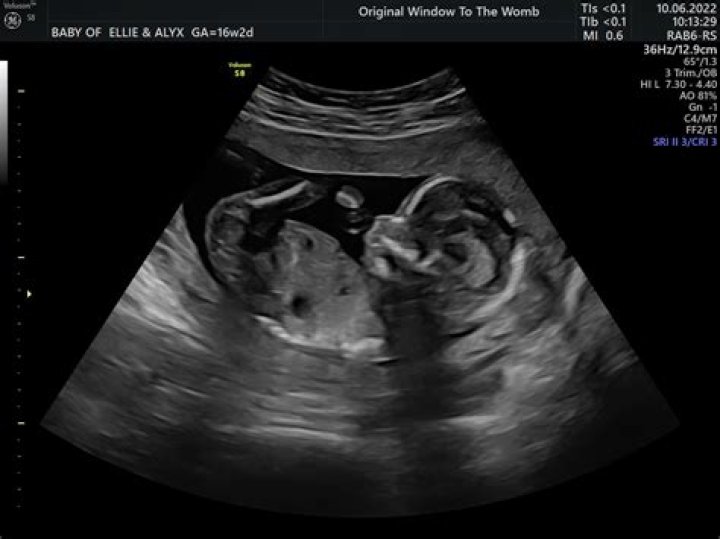

What can you see on a 16 week ultrasound?

During the 16-week scan, you can expect to see a baby that is fully formed but just very small. But, if their development is on track, you should still be able to see arms, legs, fingers, toes, and even facial expressions during the ultrasound.

What does a 16 wk fetus look like?

At 16 weeks, your fetus is now the size of an apple. Your little one could be more than 4 1/2 inches long, crown to rump, and weigh close to 4 ounces. It can be hard to imagine what your baby looks like, nestled inside the amniotic sac in your uterus.

16 weeks onwards It is possible to perform an early anomaly scan of your baby from 16 weeks. Baby’s, face, Brain, spine, limbs, kidneys heart are seen to rule out major abnormalities such as spina- bifida. Measurements are taken to ensure baby is growing normally within the womb and position of placenta is noted.